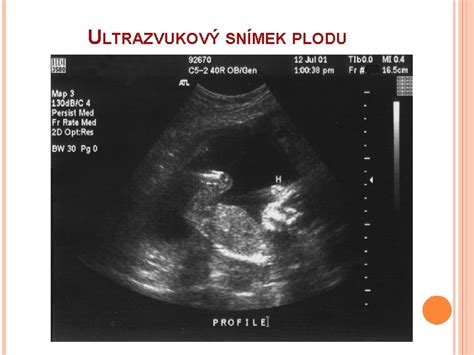

- První ultrazvuk: Obvykle kolem 6.-8. týdne těhotenství, kdy je možné vidět srdeční akci plodu.

- Potvrzení srdeční akce: Klíčový moment, který potvrzuje, že se těhotenství vyvíjí.

- Další kontroly: Pravidelná sledování u lékaře pro zajištění zdravého vývoje plodu.